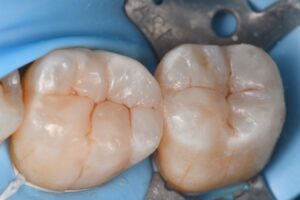

Restorative: Kerr #Simplishade Medium | Kuraray #Clearfil Majesty Flow

Matrix system: #Garrison Compositight